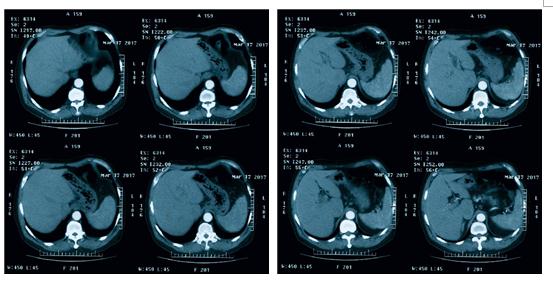

上腹部CT增强:食管胸段增厚,左心房水平食道内软组织结节,局部管腔变窄;胆囊未见显示;双侧肾上腺外侧肢稍饱满;十二指肠憩室;肝胃韧带区及腹主动脉旁多发小淋巴结,部分稍饱满(图5)

图5